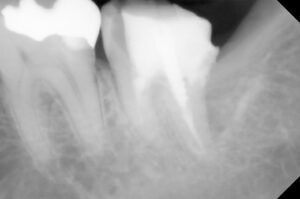

同年1/29 できてきたファイバーコアの土台をset

保険診療であれば仮歯調整して今回は終了し

次回形成と印象になりますが

患者さんに時短の説明をし納得いただけたので

続けて形成した後に印象を取り仮歯の調整まで

2時間超で自費診療:26000円+技巧代7600円

同年2/19 最短で根の処置から被せるまでこぎ着け

E-max set 自費:75000円

レントゲンでは神経の詰め物の状態の違い→

歯根の崩壊度は経時的なもの?→